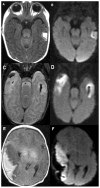

Methods: We completed a retrospective review of infants born ≥34 weeks of gestation, diagnosed with vein of Labbé thrombosis, and/or infarction on neuroimaging during the first 30 days of life. Size of each temporal lobe infarction was estimated based on the number of temporal lobe segments involved. Primary outcomes were the presence of major neurodevelopmental impairments in childhood and Bayley scores at two years.

Results: Our cohort of 19 infants had a median gestational age of 38 weeks (interquartile range 36 to 39) and mean birth weight 2892 ± 920 grams. The most common presenting symptoms of vein of Labbé thrombosis and infarction of surrounding tissue were seizures, apnea, lethargy, and either hypertonia or hypotonia. At the latest clinical follow-up appointment documented in the electronic medical record (mean 4.4 ± 3.08 years), 44% had major neurodevelopmental impairment. Patients with large vein of Labbé infarctions had significantly worse average Bayley scores than those with small to moderate lesions, and differences in language composite were statistically significant (72.7 vs 107.8, P = 0.017).

Conclusions: Neonates with large vein of Labbé infarctions are more likely to have poor language outcomes. This finding suggests a need for targeted surveillance to ensure early identification of deficits and referral for intervention.